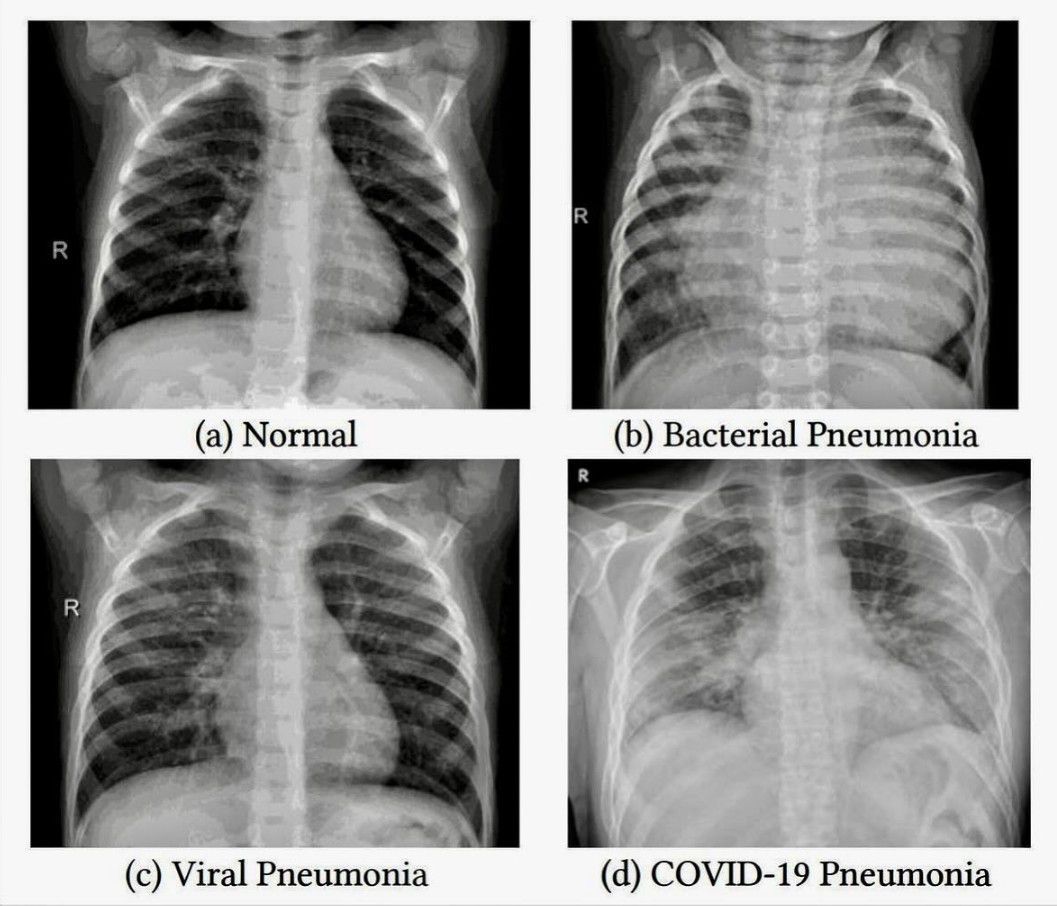

Chest X-ray Review

Here is some important information to review.